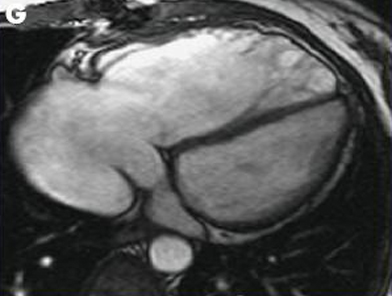

Magnetic resonance imaging (MRI) in a patient with pulmonary regurgitation following repair of tetralogy of Fallot. The patient has a non-restrictive right ventricle, and MRI shows that the right ventricle is dilated

From: Chaturvedi RR, Redington AN. Heart. 2007 Jul;93(7):880-9; used with permission